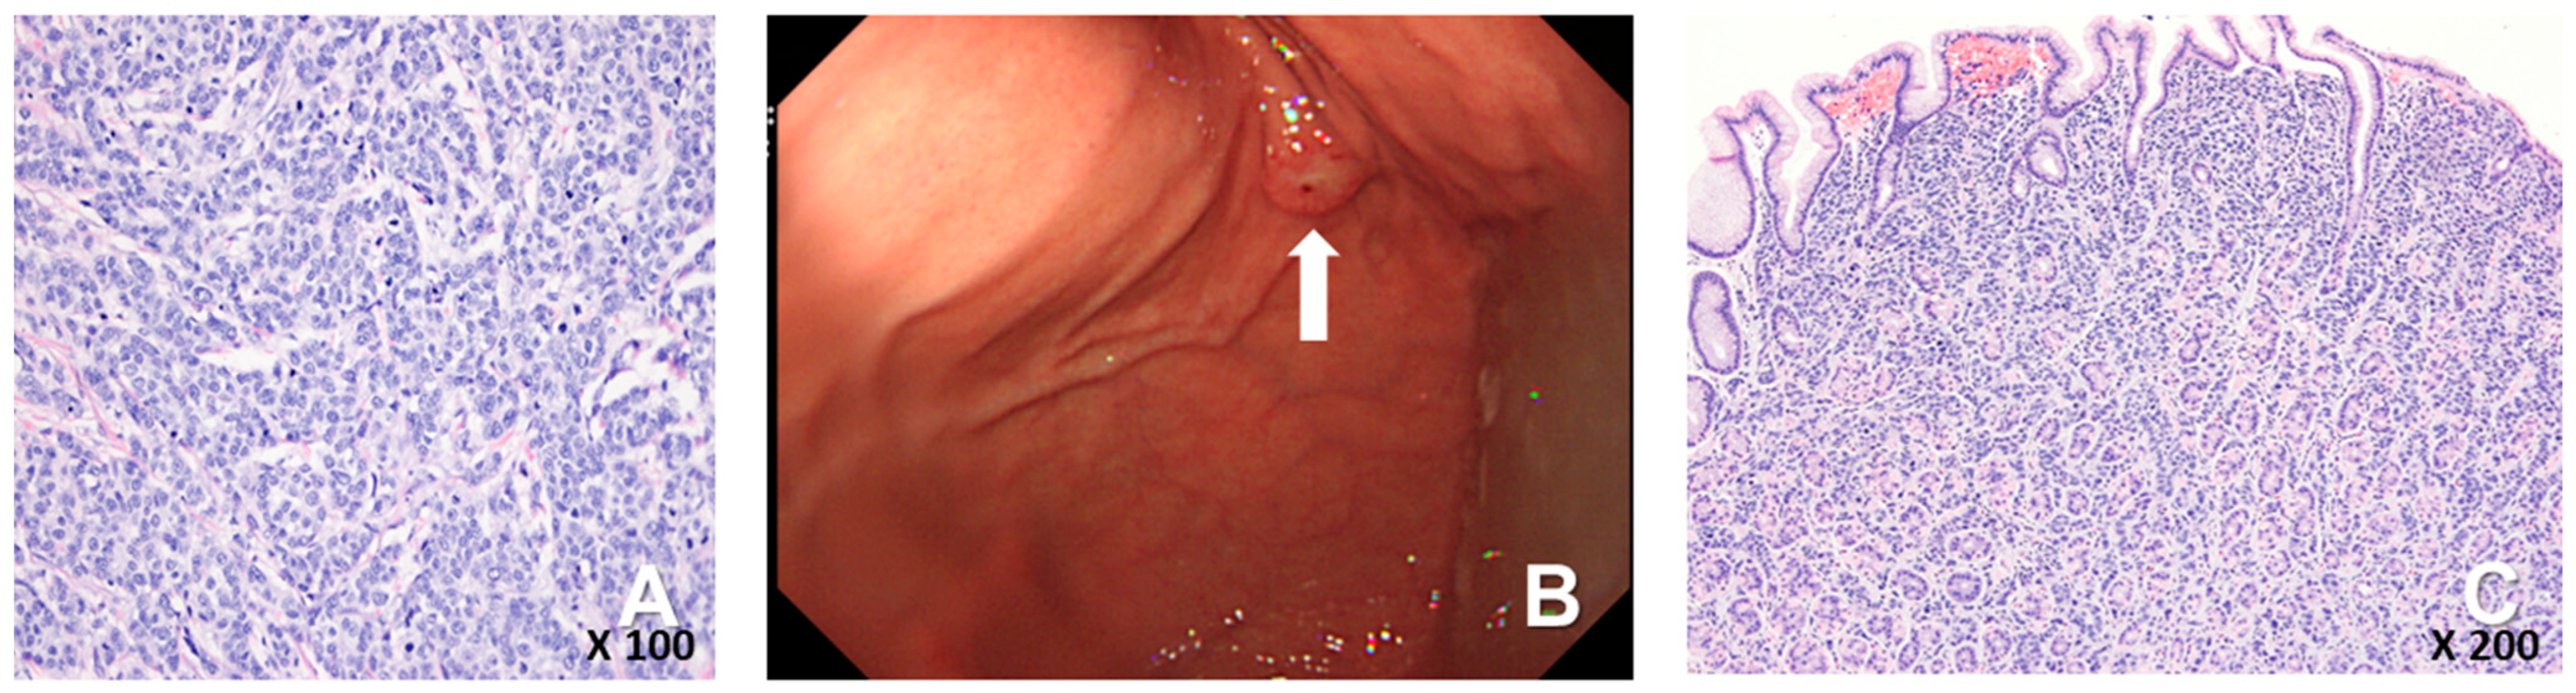

A 72-year-old female woman visited the outpatient clinic for rectal high-grade dysplasia detected during a screening test. She had a history of total thyroidectomy for thyroid cancer 25 years ago. She was admitted for endoscopic submucosal dissection for rectal cancer, and a mass in the right breast was observed during physical examination at admission. She received endoscopic submucosal dissection for rectal cancer, and ultrasonography-guided breast gun biopsy was performed during admission. On pathologic examination of the patient’s rectal cancer, the size of the tumor was 1 cm, and it was a moderately differentiated adenocarcinoma with mucosal invasion. She no longer received additional treatment for rectal cancer. During an ultrasonography examination of the right breast, a 4.9 × 4.4 × 2.2 cm irregular spiculated heterogenous echoic mass was observed. Pathologic examination revealed invasive ductal carcinoma, nuclear grade 2/3, and metastatic ductal carcinoma in the right axillary lymph node. Neoadjuvant chemotherapy, which was combined with Adriamycin, cyclophosphamide, and docetaxel, was performed. After four cycles of neoadjuvant chemotherapy, partial remission was observed. She underwent right modified radical mastectomy (MRM). Postoperative pathological examination revealed invasive ductal carcinoma, and pathologic stage ypT3(8 × 7 × 2.3 cm)ypN3(22/29). Immunohistochemical staining for estrogen receptor (ER), progesterone receptor (PR), and human growth factor receptor 2 (HER-2) were all negative (Figure 1A). After surgery, adjuvant chemotherapy based on capecitabine was performed along with radiation therapy. Nine months after MRM, gastroscopy was performed because of epigastric pain and discomfort. A gastroscopy revealed a 1 cm sized elevated mass in the posterior wall of the fundus, and endoscopic biopsy was performed (Figure 1B). Microscopic examination of the biopsy specimen showed solid nests or cords of tumor cells with histologic features resembling poorly differentiated carcinoma at initial diagnosis (Figure 1C). Immunohistochemical staining for GATA3 (GATA binding protein 3) and gross cystic disease fluid protein-15 (GCDFP-15) was carried out to rule out the possibility of metastatic breast cancer. Since both markers were negative in both breast cancer and in gastric cancer, it was inconclusive for determining the origin of the gastric tumor (Figure 2A–D). Moreover, the small size of the biopsy specimen itself brings limitations in evaluating the histologic features of entire gastric tumor. Therefore, a resection of the entire mass was needed. As the tumor cells were poorly differentiated, gastrectomy was considered more than endoscopic resection. Preoperative examination, including abdomen-pelvis CT and chest CT, was performed to check for distant metastasis, and no evidence of distant metastasis was found. She underwent totally laparoscopic total gastrectomy 10 months after MRM. The patient was diagnosed with T1bN1M0 gastric cancer according to AJCC 8th edition. Gross examination of the resected specimen revealed a well-demarcated mass measuring 1 × 0.7 cm. The entire mass was microscopically examined, and a poorly differentiated carcinoma that invaded the submucosa was identified; however, it differed from the general histological features of primary gastric adenocarcinoma for the following reasons: (1) No surface epithelial cells showed dysplasia or malignant change. (2) All tumor cells were located in the lamina propria with a solid nest or cord patterns with no glandular growth pattern (Figure 3A). Therefore, the tumor was more likely to be metastatic breast cancer than primary gastric cancer. It was reviewed again with the pathological findings of previous BC, and the histologic features of breast cancer and gastric cancer were almost identical. Additionally, cytokeratin CK 7 (CK7) immunostaining showed diffuse and strong positivity in both the gastric and breast specimens (Figure 3B,C). As a result, possible gastric metastasis of BC was diagnosed because the histological shape and immunohistochemical staining findings were consistent with BC. After the totally laparoscopic total gastrectomy, the patient received palliative first-line chemotherapy with paclitaxel and cisplatin (CDDP). Two months after gastrectomy, she was diagnosed with para-aortic lymph node metastasis and multiple bone metastases (Figure 4A,B). She underwent hip arthroplasty due to pathologic fracture of the right hip joint three months after gastrectomy, and she expired six months after gastrectomy.

Figure 1. (A) The breast cancer consisted of solid nests or cords of tumor cells, which was consistent with the diagnosis of invasive ductal carcinoma (H-E staining, ×200). (B) Endoscopy showed about 1 cm sized elevated out in posterior wall of gastric fundus, (white arrow). (C) The biopsy specimen of the gastric tumor showed poorly differentiated carcinoma with no glandular differentiation (H-E staining, ×100).